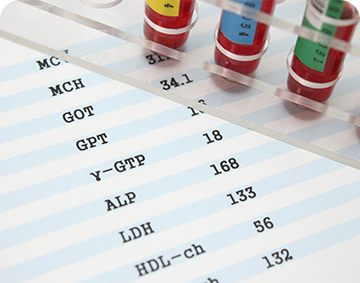

より精度の高い診断を行うため、院内にはマルチスライスCTや呼気NO検査、肺機能検査装置、血液検査装置などの先端設備を備えています。身体の微細な変化や気道の炎症を数値で捉えることで、根拠に基づいた的確な治療が可能です。迅速かつ精密な検査体制を整えることで、病気の早期発見と早期治療を強力にバックアップします。

血液検査